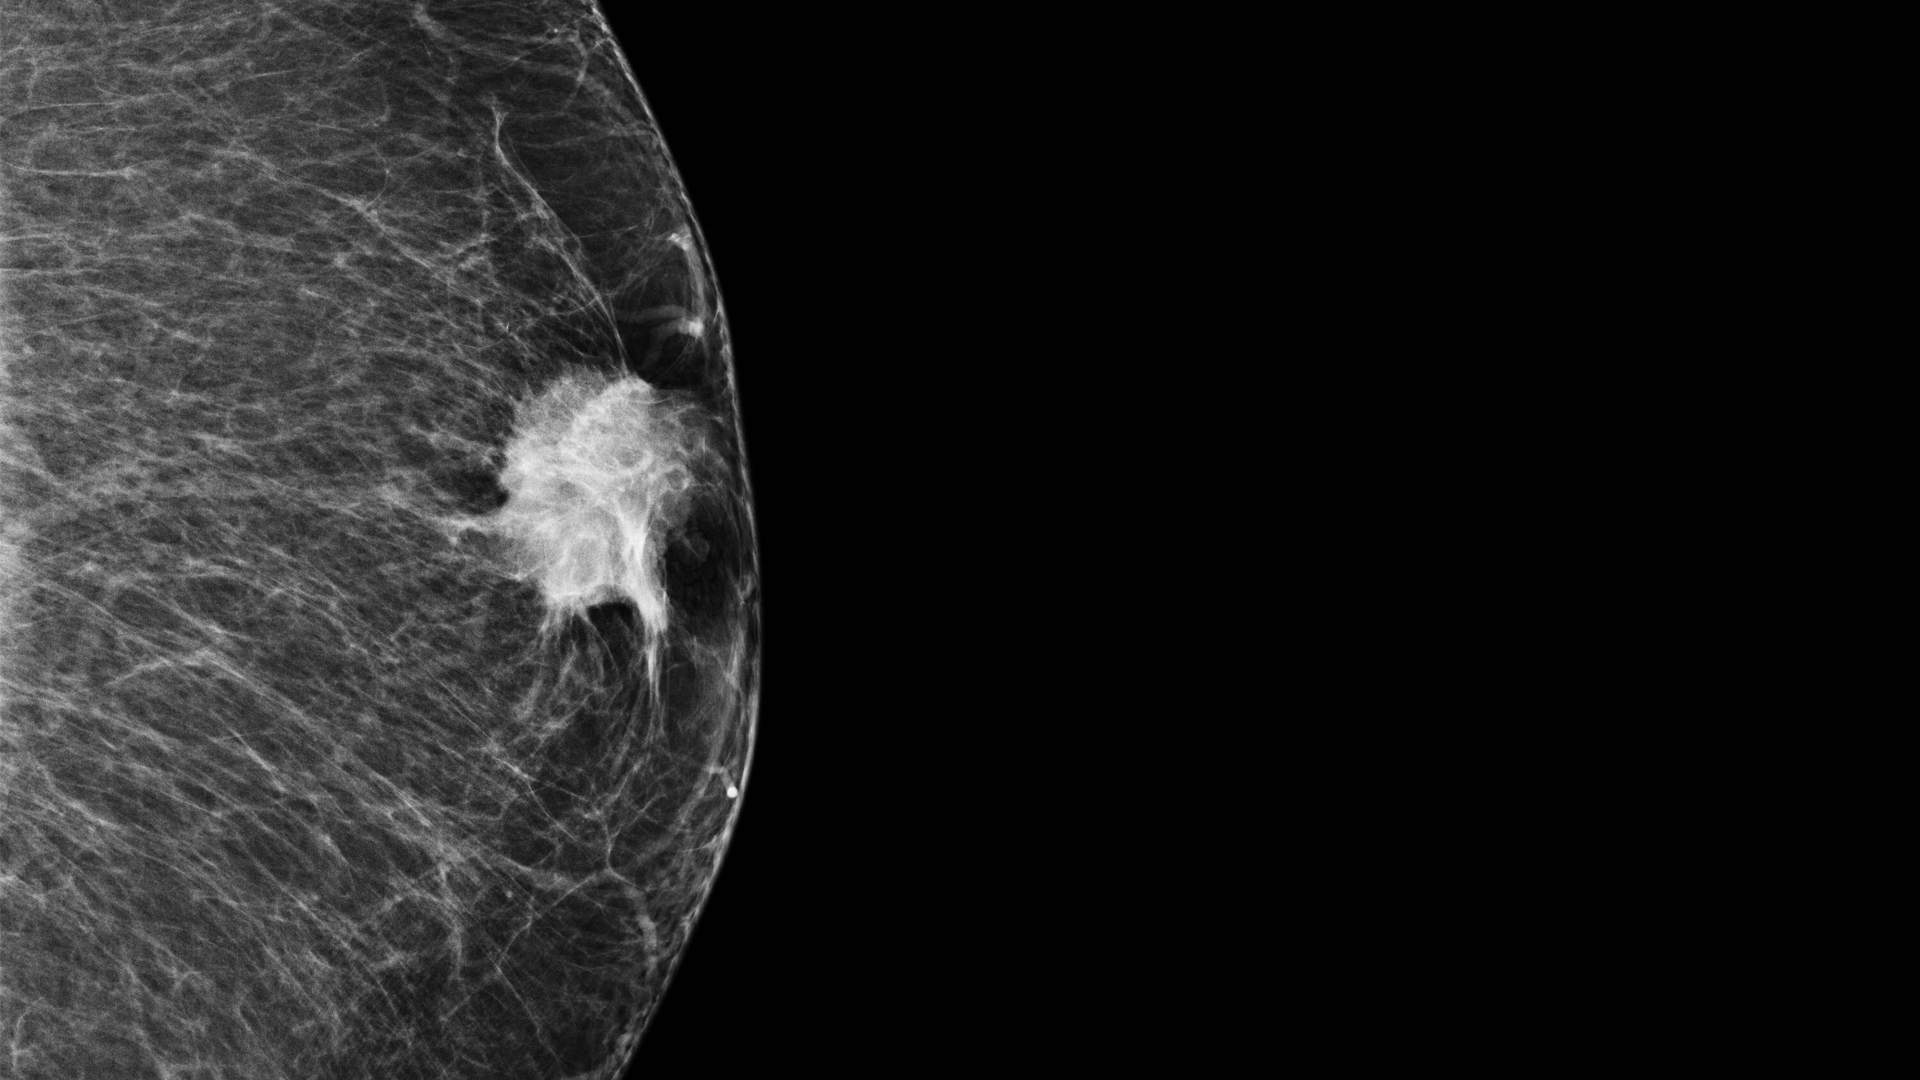

Beeld: Mammografiebeeld van een mannelijke borst met tumor. Credit: Ann Smeets